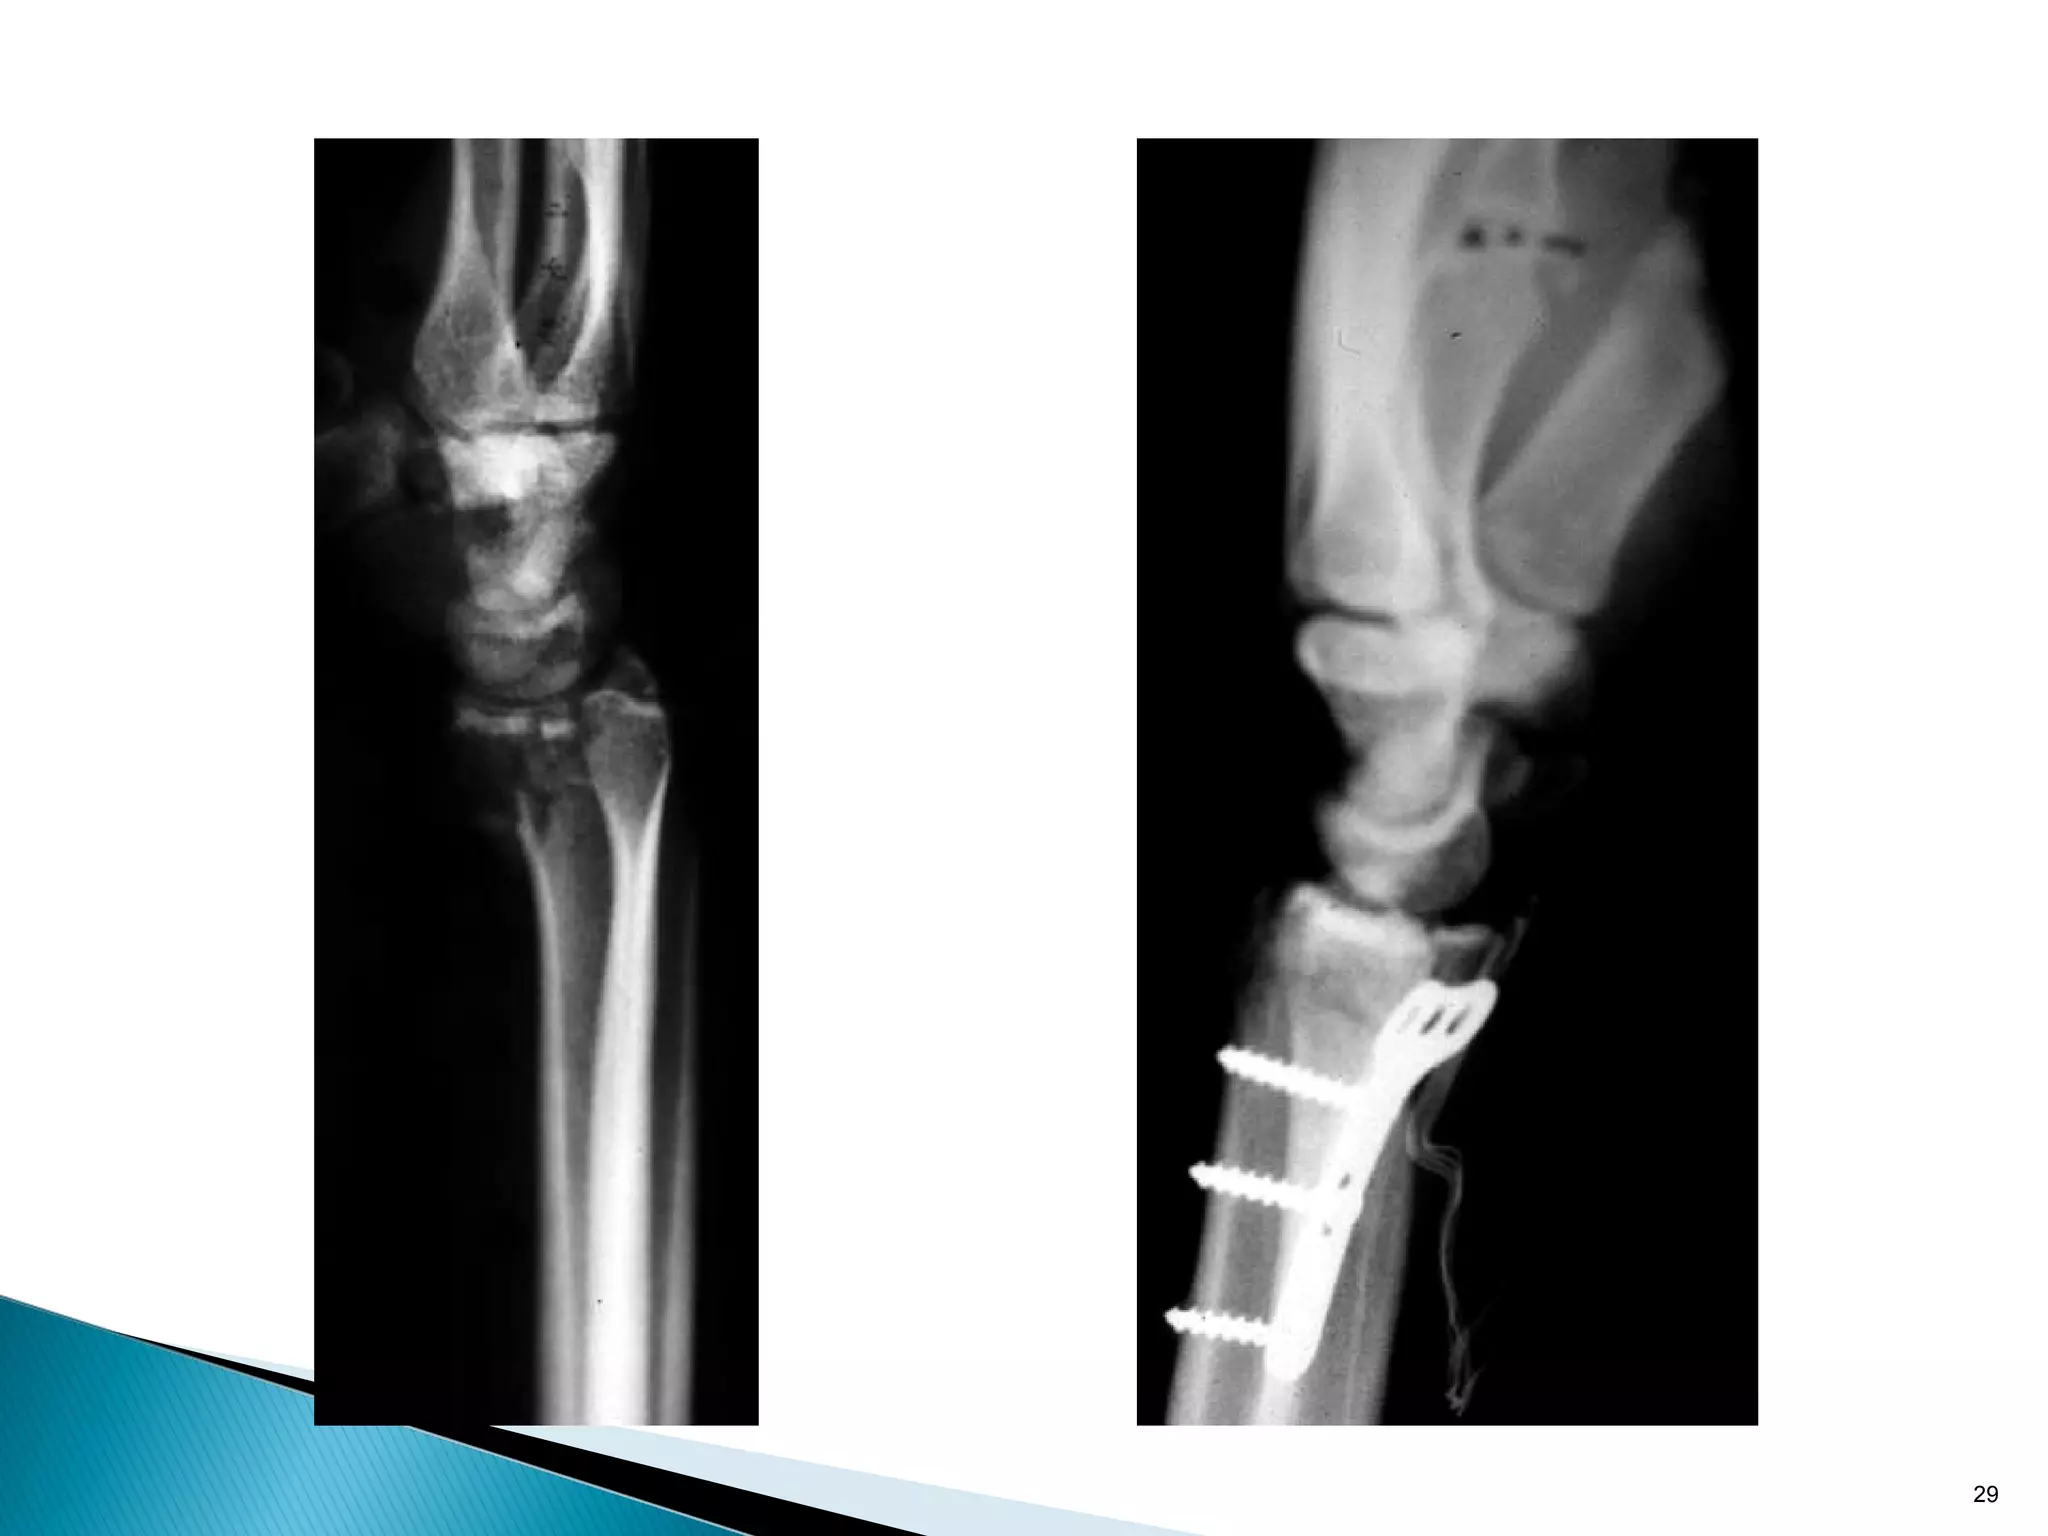

• Used when the fracture will only displace in one direction

• Only useful in metaphyseal fractures

• Applied so as to resist one deforming force

26

• Used whenthe fracture will only displace in one direction • Only useful in metaphyseal fractures • Applied so as to resist one deforming force 25